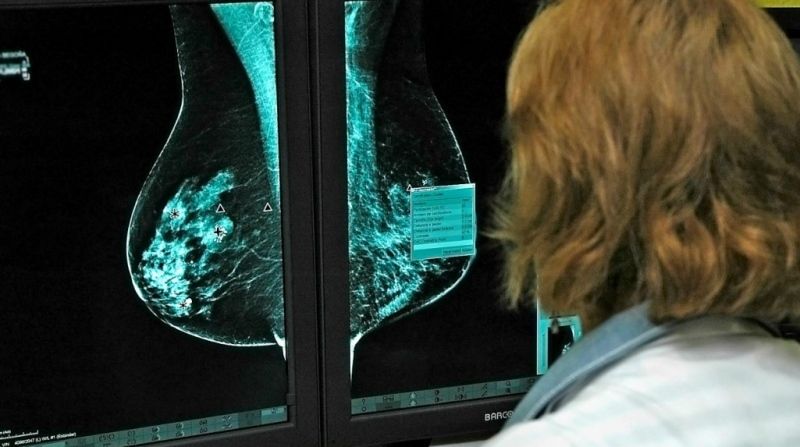

El Hospital General Universitario de Ciudad Real abre una nueva línea de investigación sobre el cáncer de mama

El Hospital General Universitario de Ciudad Real, dependiente del Servicio de Salud de Castilla-La Mancha, ha abierto una nueva línea de investigación relacionada con el cáncer de mama. El objetivo es determinar si se puede minimizar la agresión de la cirugía en los dos tipos de cáncer de mama más agresivos, el triple negativo y el Erb positivo,  manteniendo el máximo control de la enfermedad.